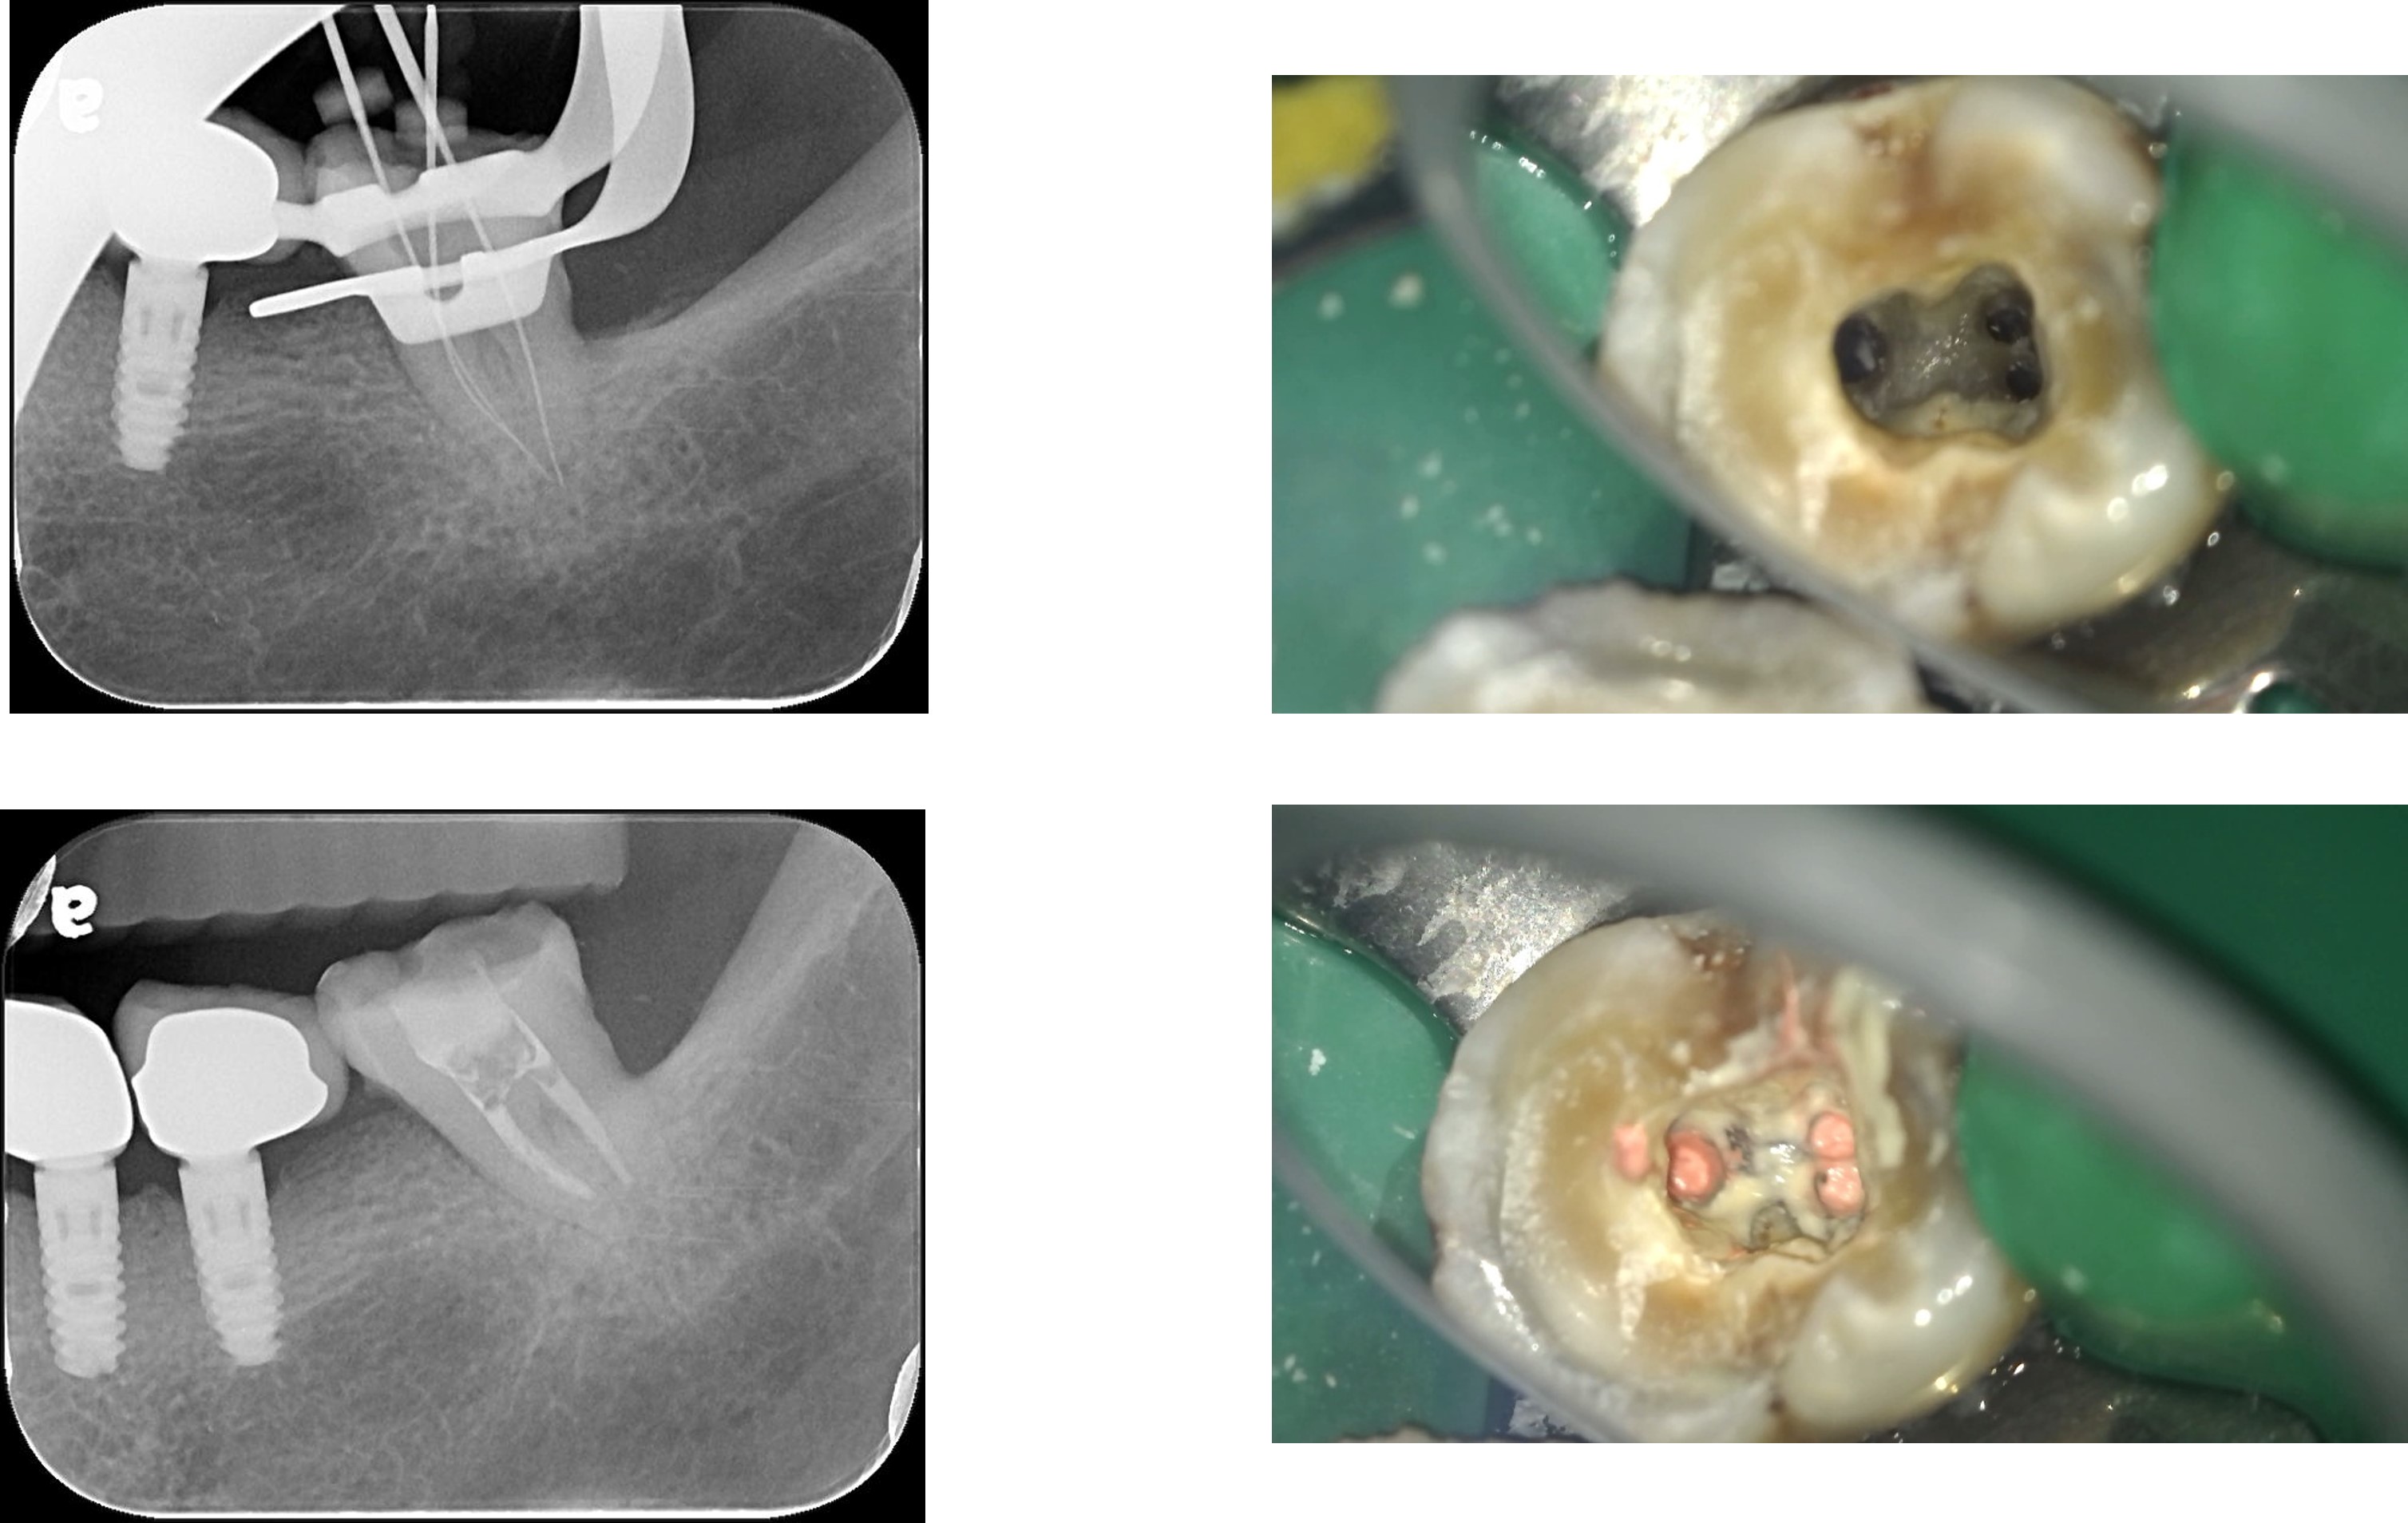

顯微根管治療:#37

顯微根管治療:#27

左下顎牙冠增長手術